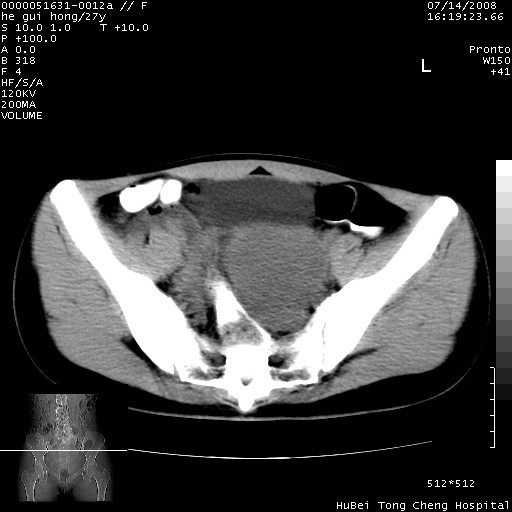

以下是引用杀毒软件在2008-7-20 8:03:00的发言:[br]支持双侧卵巢囊腺瘤可能性大!

以下是引用zjzjr在2008-7-20 13:36:00的发言:[br]双侧附件囊腺瘤可能性大!